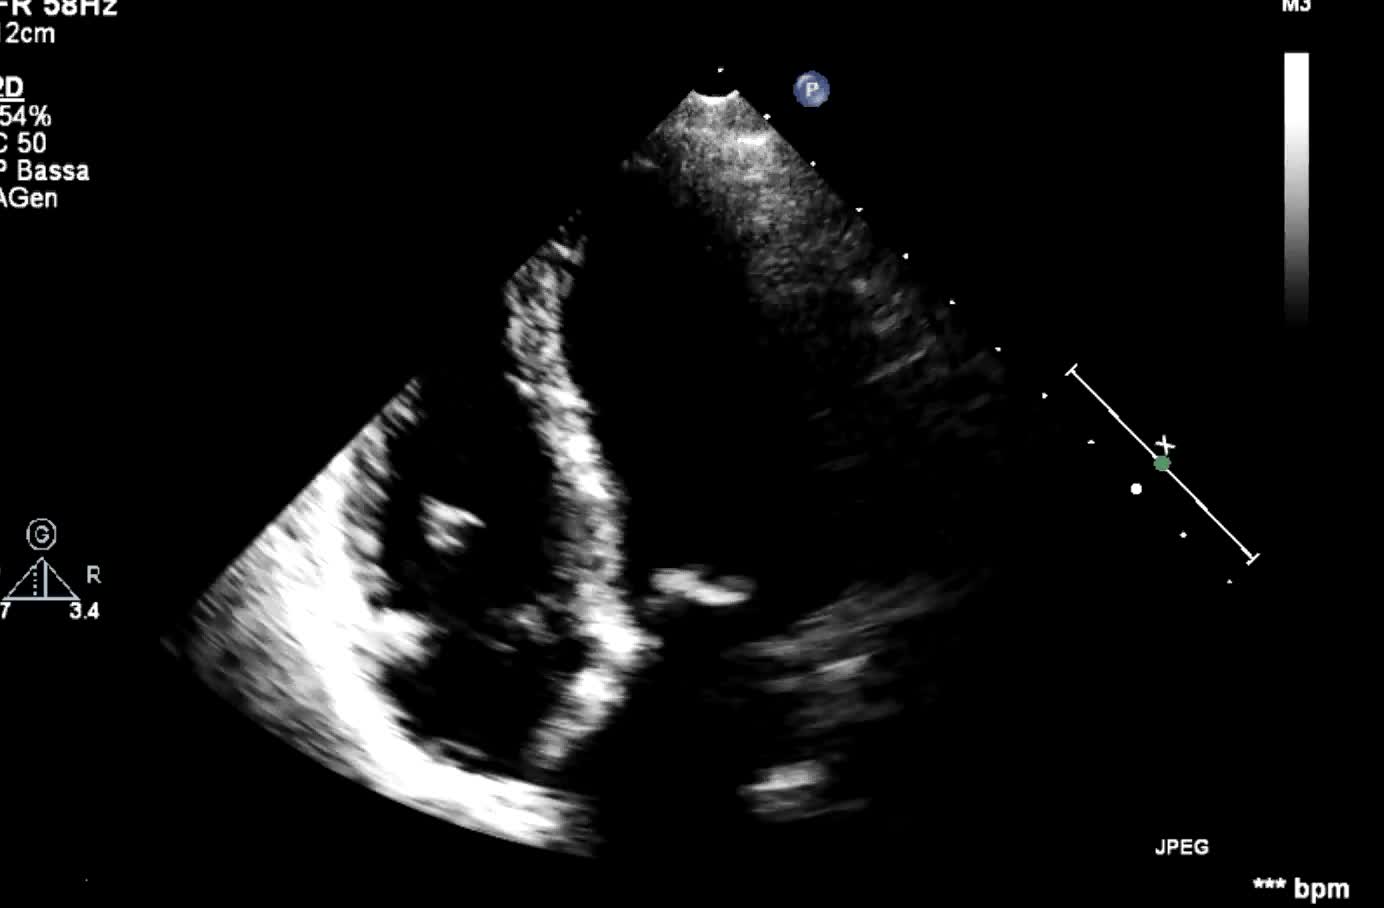

Megaatrio sinistro

Autore:

Oscar Gaddi